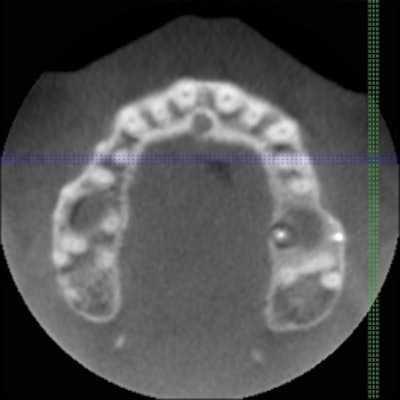

An advantage to large fields of view would be to determine symmetry. Occasionally there will be a lesion present and the need for a scan on the opposite arch is helpful in determining if it is normal. Also when there are difficult teeth to treat, a full scan of one arch can be helpful in determining whether extra canals are truly evident. For example, a retreatment case that is difficult to determine if a 2nd, 3rd, or 4th canal is present due to the prior treatment can also be viewed with its counterpart. If a canal is demonstrated in its counterpart, there will surely be one in the case in question.

| Cone beam CT images can provide axial views not possible with traditional 2D imaging. |

Also with a single-arch scan, sinus infections or abnormal sinuses can be shown to the patient. For example, a patient who has had an infection in the upper first molar had complications with the sinus that was easily detected with a 4 cm single-arch scan. By viewing the opposite side, the sinuses were clear in one side while the arch in question had some type of irritation present in it. Also with a full-arch scan, another patient had a break in the sinus and the infection was draining right into it.

Note that single-arch scans are not full upper- and lower-arch scans. Full upper- and lower-arch scans can be done, however, enabling easy diagnosis of the entire mouth. For example, we took a full upper and lower arch scan and determined other pathology not noted from the referring dentist or from regular bitewing checkups.